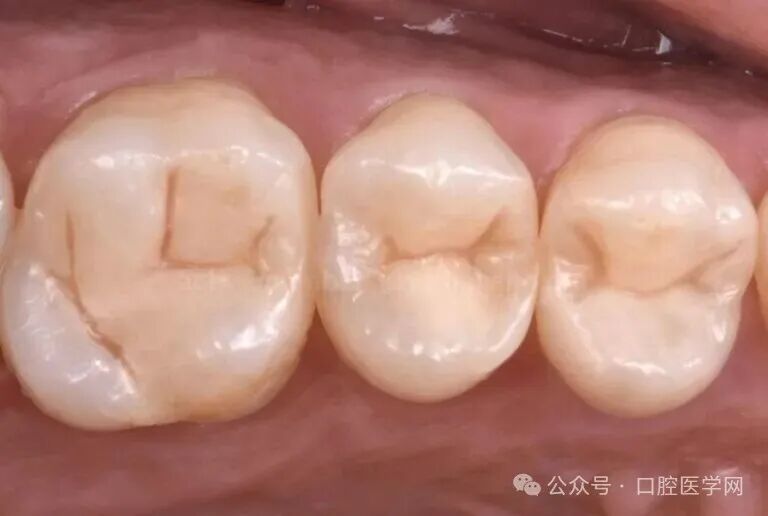

图1

初始临床情况。第一象限可见多处龋损,以及发生渗漏、老化的复合树脂修复体。结合患者需求,所有修复操作均规划并完成于单次临床就诊中。